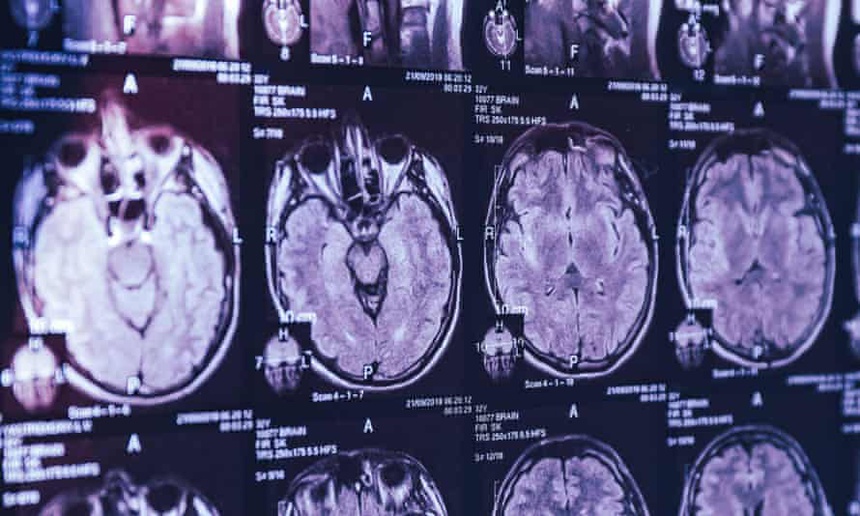

Hàng loạt người ở Canada mắc những triệu chứng nổi bật của một chứng bệnh được các bác sĩ ở nước này chẩn đoán là chưa từng được biết đến trước đây, vì những những triệu chứng căn bệnh như co thắt cơ bắp, mất trí nhớ và ảo giác.

Ít nhất 43 bệnh nhân ở vùng Acadian thuộc tỉnh New Brunswick, Canada, được chẩn đoán mắc bệnh lạ liên quan đến vấn đề thần kinh.

Người mắc bệnh thần kinh lạ ở Canada có triệu chứng co thắt cơ bắp, mất trí nhớ và ảo giác. Ảnh: Alamy Stock Photo.

Một số triệu chứng bao gồm tình trạng mất trí nhớ, các vấn đề về thị lực và động kinh.